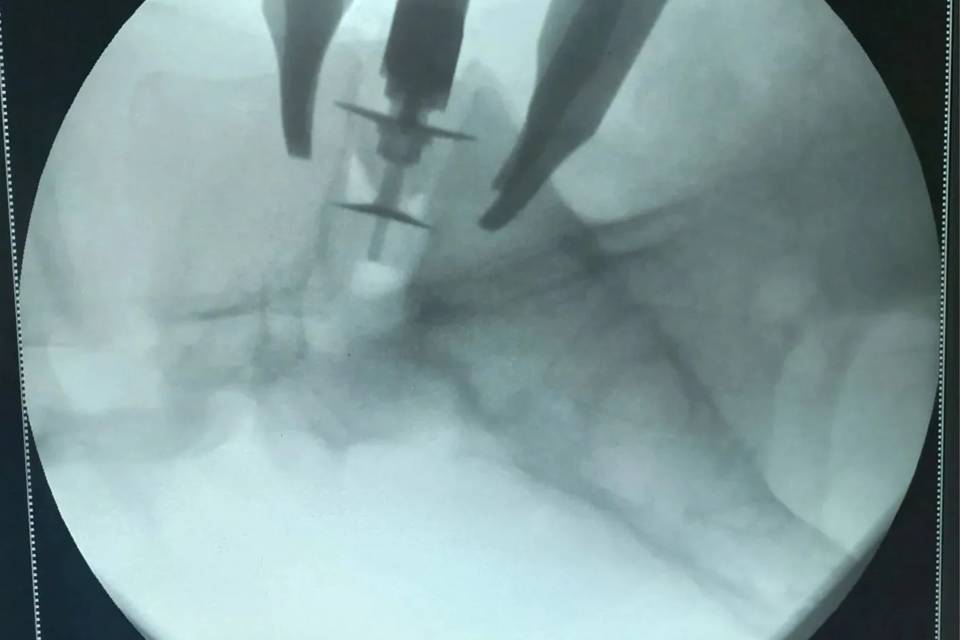

В Региональном нейрохирургическом центре Волгоградской областной клинической больницы №1 внедрили операцию под названием артродез позвоночника с передним внебрюшинным доступом, или ALIF.

Суть методики в том, что хирург работает с передней части позвоночника. Это позволяет полностью удалить поврежденный межпозвонковый диск и установить имплантаты, которые фиксируют позвонки в правильном положении, увеличивают расстояние между ними и освобождают сдавленные нервные корешки. Такой подход сводит риск рецидива грыжи почти к нулю.

Еще один плюс - передний доступ не травмирует мышцы поясницы, поэтому пациенты восстанавливаются быстрее.В Волгограде уже провели три такие операции: две на уровне L5–S1 и одну на уровне L3–L4. Все вмешательства выполнили пациентам с грыжами, которые сопровождались сдавлением нервных корешков и сильными болями в спине и ноге. Операции прошли с минимальной кровопотерей и травмой тканей. Пациенты чувствуют себя хорошо и готовы вернуться к обычной жизни.

Один из хирургов, Евгений Гридин, вместе с коллегой Игорем Корниловым провел эти вмешательства. Руководитель центра, главный нейрохирург ЮФО Петр Кушнирук, пояснил: в планах сделать такую высокотехнологичную помощь рутинной для больницы.